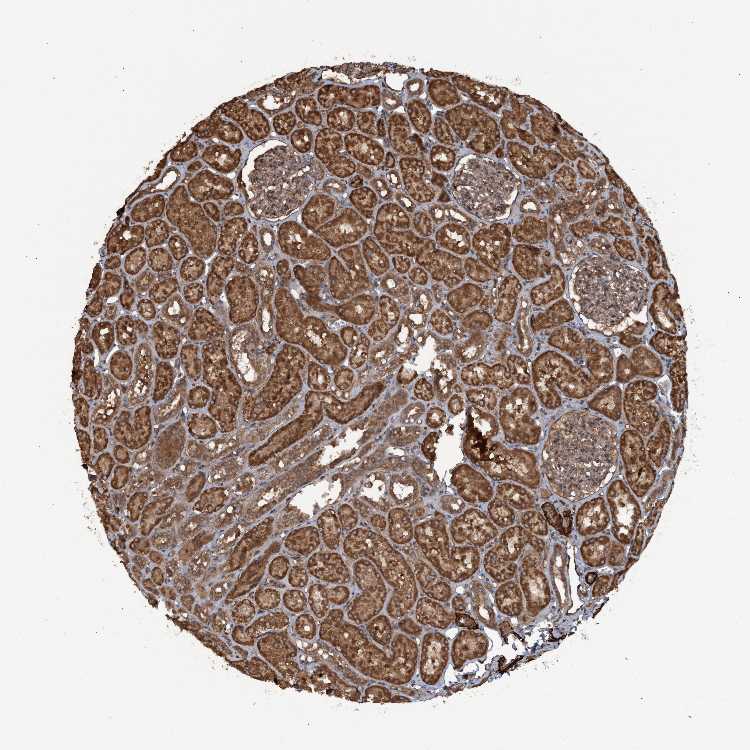

TISSUE PRIMARY DATA KIDNEY Show tissue menu

Kidney

KIDNEY - Expression summary

Protein expression

Kidneyi

On the top, protein expression in current human tissue, based on all annotated cell types, is reported with the units not detected (n), low (l), medium (m) and high (h). Underneath, protein expression in each annotated cell type are reported using the same units.

Protein expression data is based on knowledge-based annotation. For genes where more than one antibody has been used, a collective score is set.

If knowledge-based annotation could not be performed for a gene, no data is displayed here. View antibody staining data further down this page.

Cells in glomeruli: Medium

Cells in tubules: High

KIDNEY - Antibody stainingi

Antibody staining in the annotated cell types in the current human tissue is reported as not detected, low, medium, or high, based on conventional immunohistochemistry profiling in selected tissues. This score is based on the combination of the staining intensity and fraction of stained cells.

Each image is clickable and will lead to virtual microscopy that enables deeper exploration of all samples and also displays staining intensity scores, fraction scores and subcellular localization as well as patient and tissue information for each sample.

Antibody HPA023362Antibody HPA027213

Cells in glomeruli MediumNot detected

Cells in tubules HighMedium